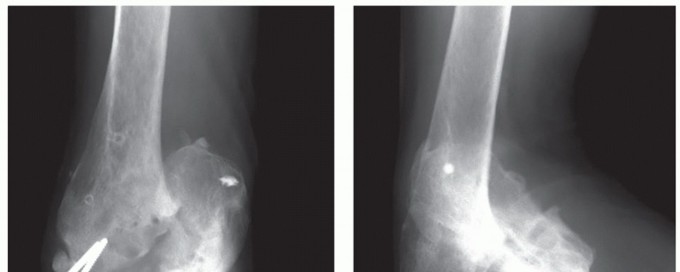

DEFINITION Brett D. Owens Joanna G. Branstetter Thomas P. Goss Intra-articular scapular fractures include fra…